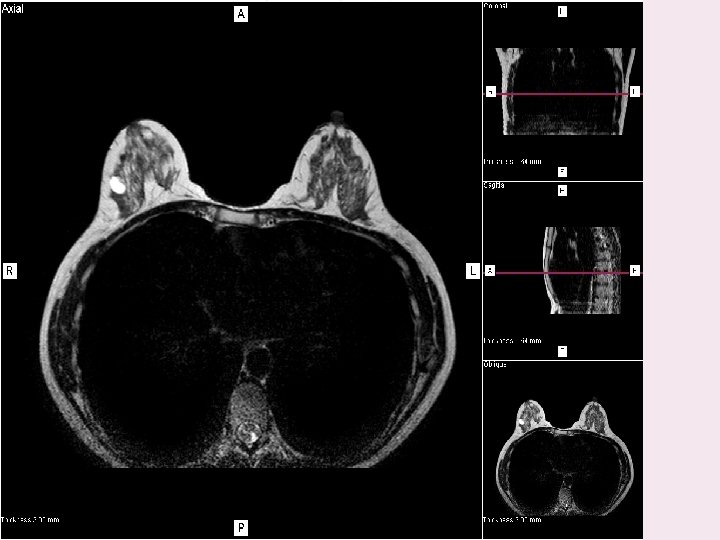

TECNICA DE SUSTRACCION

RESULTADO SUSTRACCION